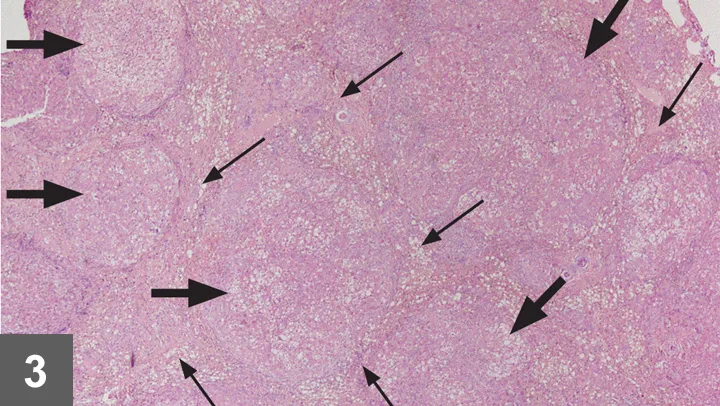

• Changes in hepatic echogenicity occur in acute and chronic liver disease (Figure 2).

• Ultrasonographic changes are usually not specific for a particular disease.

• The liver can also appear ultrasonographically normal, even in severe disease.

FIGURE 2 Ultrasonographic image demonstrating a diffusely mottled and nodular appearing hepatic parenchyma.